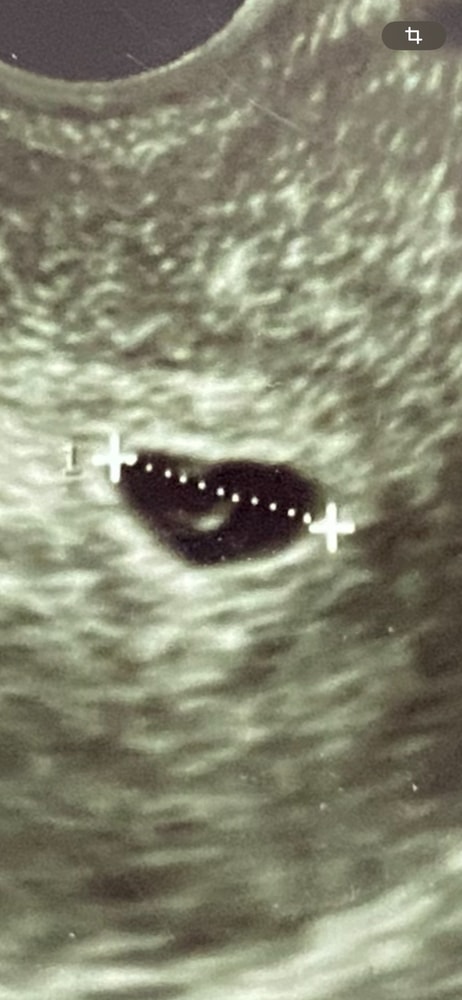

Всем здравствуйте! Моя беременность началась со странностей .. задержка несколько дней и мажущие выделения, делаю тест положительный, но полоска очень бледная еле еле видно, так как мазало, я испугалась, что это может быть внематочная и поехала на узи, в итоге плодное яйцо не нашли при задержке 4 дня, сказали приехать позже, поехала через 13 дней плодное яйцо сразу же увидели размер 12.6 мм что соответствует 5 неделям и 4 дням написали по узи, но врач сказала что не видит эмбриона , мазать так и не перестало ..неужели эмбриона действительно нет 😭 или на таком сроке есть вероятность того, что его реально можно не увидеть ?

Фото кстати было похоже на ваше. Кружочек и почечка внутри. Подождите недельку, думаю рано.